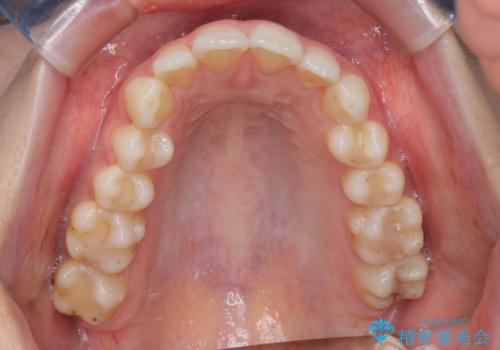

【インビザライン】前歯のガタガタをなおしたい。

- 前歯の凸凹を主訴に来院されました。

インビザラインにて奥歯の遠心移動を行いながら、前歯のガタガタを改善することができました。